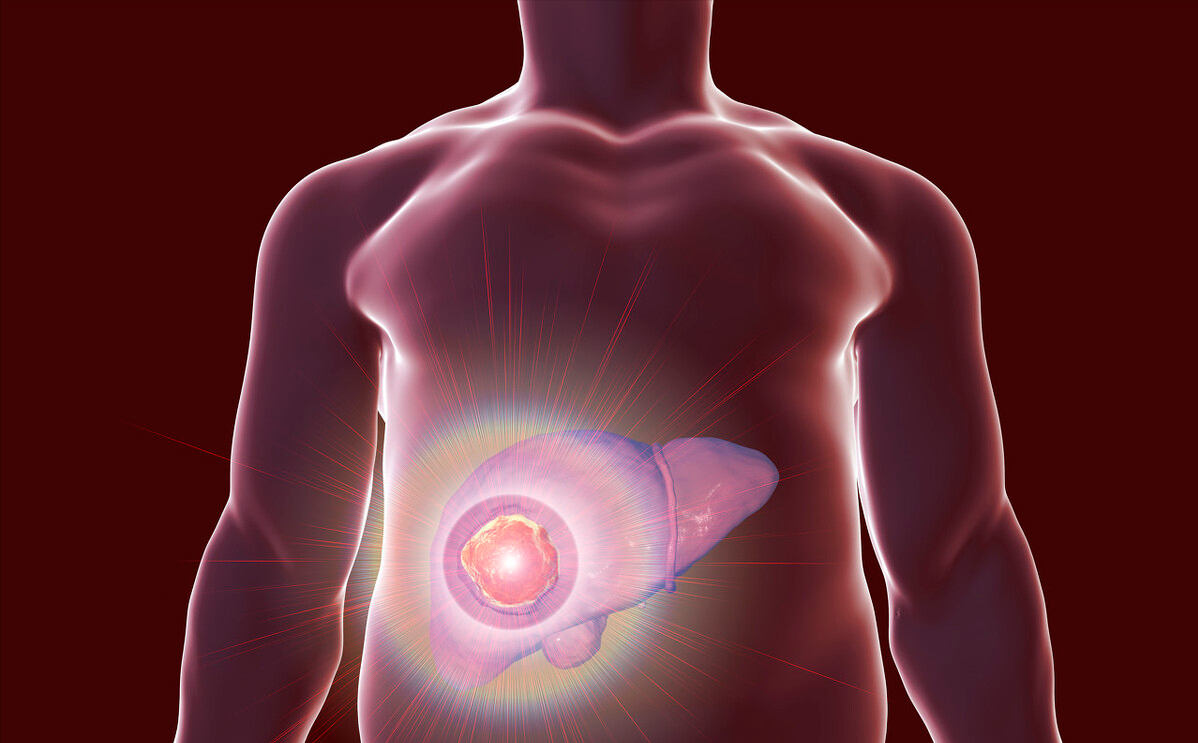

更可怕的是……往往肝癌一发现就是:晚期!

早期肝癌症状非常不明显

健康的肝脏大约只需要四分之一就可以让人体正常工作。

肝癌早期,肝脏功能往往是够用的,所以人体很可能不会有明显异常。

很多患者,直到肿瘤大得把肚子都撑起来了,才发现是晚期肝癌,即便在这时,患者的肝功能都可能还正常。